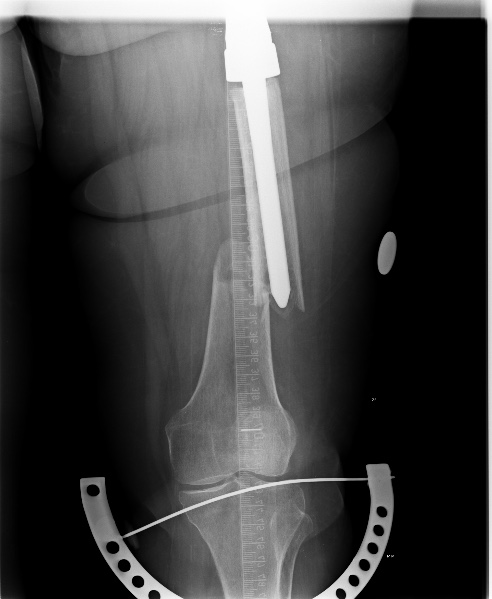

[Ortho] Перипротезный перелом

Имя     : 2.jpg

Тип     : image/jpeg

Размер  : 57676 байтов

Url     : http://weborto.net:8080/pipermail/ortho/attachments/20150205/ae2825c5/attachment-0003.jpg